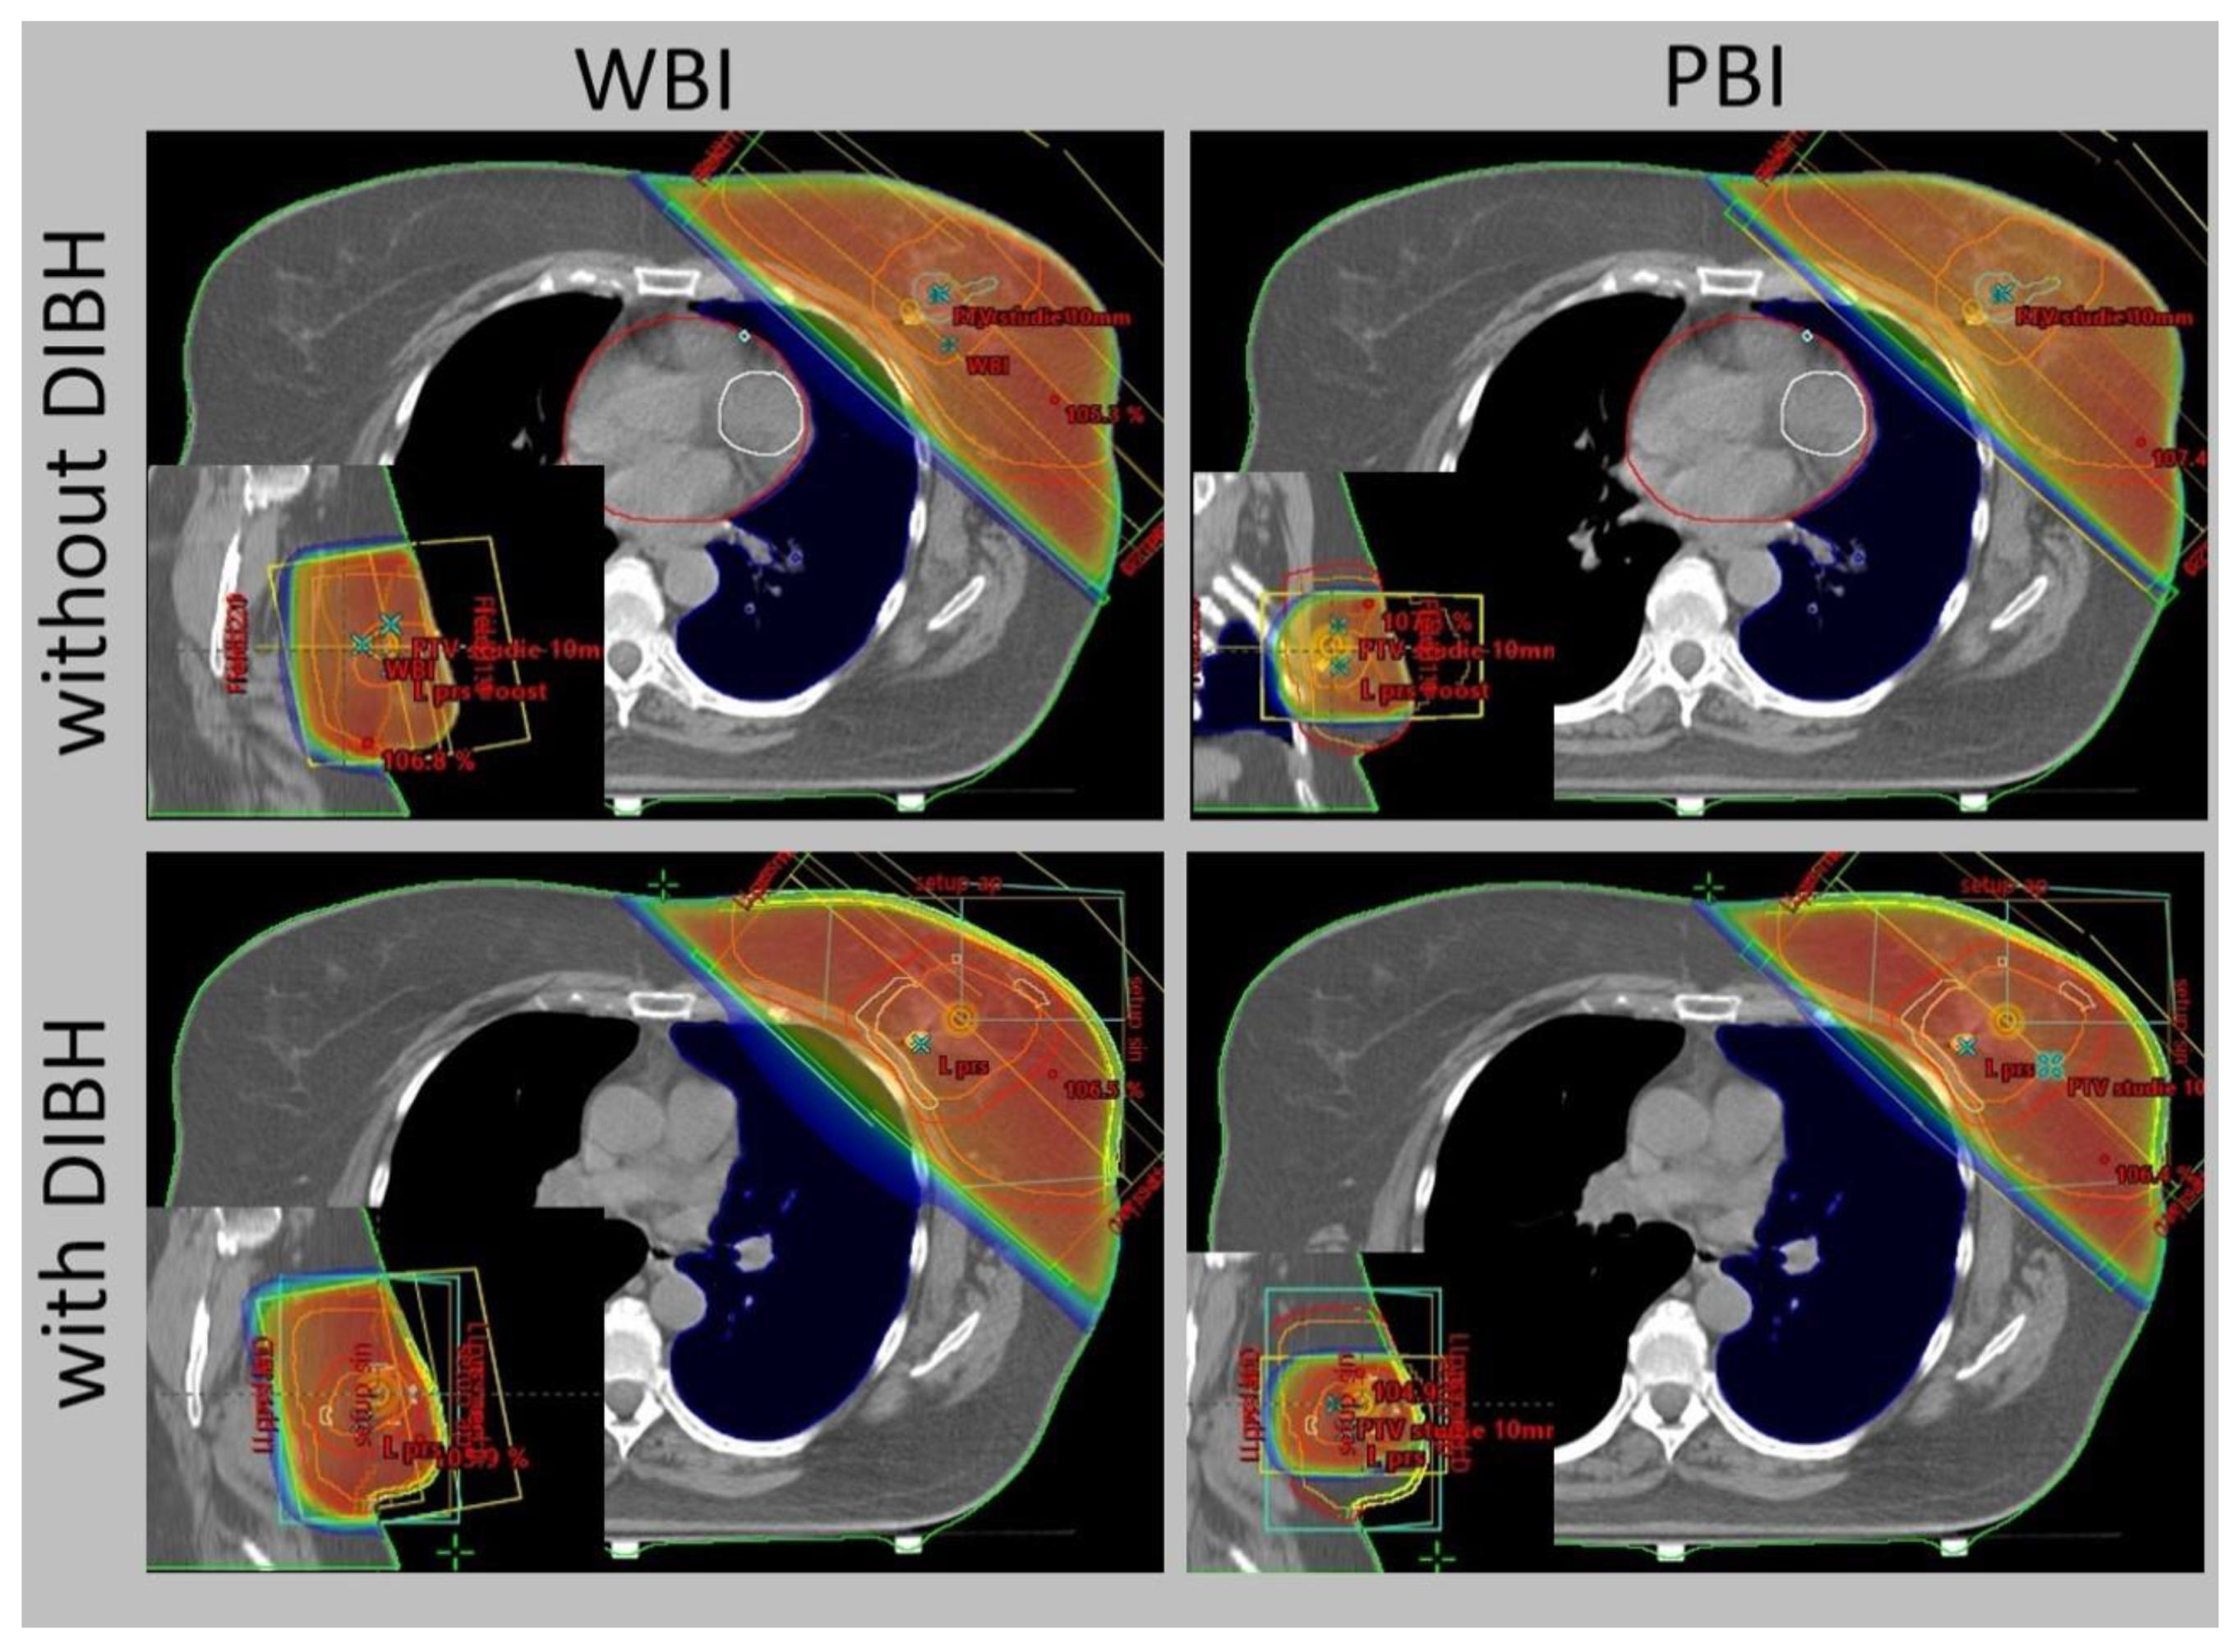

Figure 3. External-beam whole breast irradiation (WBI) and partial breast irradiation (PBI) with and without deep inspiration breath hold (DIBH) – comparison of the same target volume CT slice.

The progress in radiotherapy is based mostly on the use of new technologies. Currently. external beam radiation is performed using linear accelerators after computed tomography-based imaging (Figure 1) and 3-dimensional planning using sophisticated technologies, including intensity-modulated radiation therapy (IMRT). The control of the accuracy of the dose delivery can be increased with image-guided radiation therapy (IGRT, Figure 2). The dose to the heart can be substantially decreased by delivering radiation in deep inspiration (Figure 3) or prone position [4,5].

The use of breast-conserving surgery is also supported by the availability of the option to modify adjuvant breast irradiation that would further decrease the side effects of therapy compared to WBI. Selected subgroups of patients can be treated with less extensive radiotherapy techniques including accelerated partial breast irradiation (APBI, Figure 4), partial breast irradiation (PBI, Figure 3), or intraoperative radiotherapy (IORT) [22].